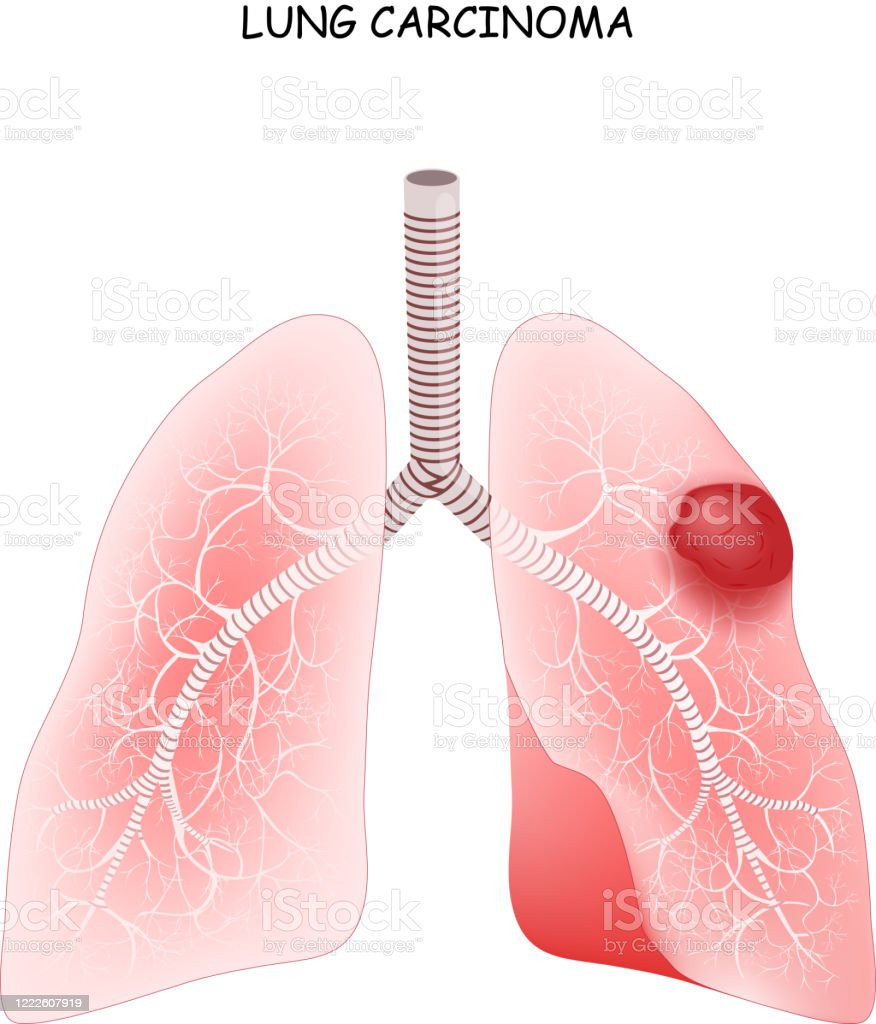

TAG: kanker paru

kanker paru

"Kanker Paru"